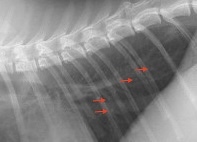

咳をする若い猫ちゃんの胸部レントゲン写真です。大きな異常は認められないですが、

拡大して肺の後ろ側をよく見ると、白いポッチのような病変(赤矢印)がいくつか確認できます。これは気管支パターンと言って、気管が腫れていることを示す所見です。この子は非常に軽い気管支パターンでしたが、喘息の治療をしたところ症状が改善しています。猫の喘息は体質が関与していると見られ、時々再発を繰り返しますが、治療への反応がよい子は普段の生活に支障がない程度に回復してゆきます。